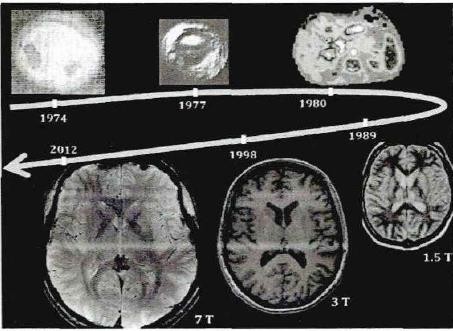

磁场的强弱是一个相对概念,医院里面的磁共振成像(简称“MRI”)常见的有1.5特斯拉(T)和3特斯拉(T)(注:1T=10000Gs)。相对于1.5T MRI,3T MRI就是强磁场了,磁场越强,MRI的分辨率越高。

图1 不同磁场强度的MRI成像(图片来源:Christakis C.Magnetic Resonance Imaging[M]. Taylar and Francis:2014)